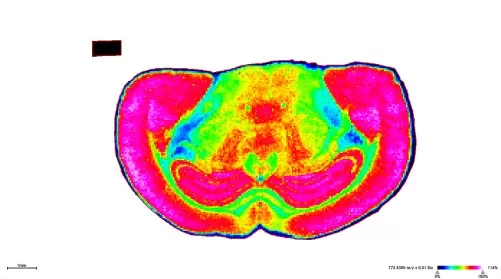

Spatial Mapping: Analysis software—such as SCiLS Lab or ImageJ—generates heatmaps indicating spatial variation in metabolite levels. Advanced statistical tools including PCA and t‑SNE further assist in revealing metabolic gradients and identifying correlations with specific tissue structures.

Heatmaps of spatial variation in metabolite levels